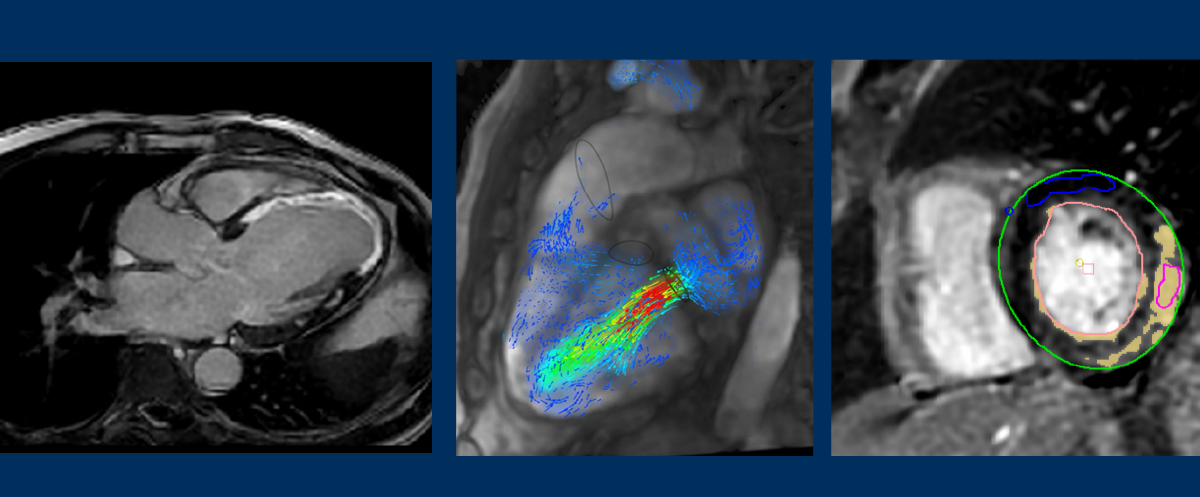

"We at Noble Imaging and Diagnostics, aim to provide complete diagnostic services including 3 Tesla MRI, CT SCAN, ULTRA SONOGRAPHY & Digital X-RAYS under one roof and with highest accuracy. Our team consists of experienced radiologists, technicians and staff who care for the patient at each step and guide them so that the process of undergoing tests becomes easy and stress free."